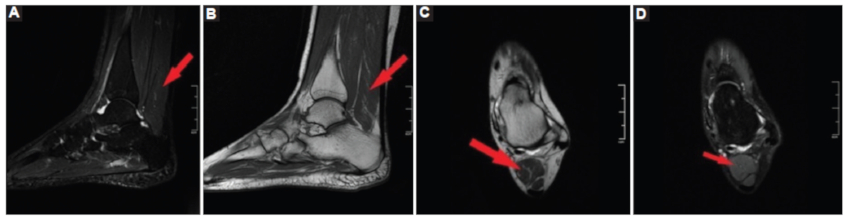

En resonancia magnética (RM), en el plano sagital en secuencias STIR (Fig. 3A) y T1 (Fig. 3B) y en plano axial en secuencias ponderadas en T2 (Fig. 3C) y DP FATSAT (Fig. 3D) se observó imagen de intensidad de señal similar al músculo en la porción posterior de la pierna, cuya inserción distal es en el margen superior del calcáneo, compatible con músculo sóleo accesorio. También se identificó aumento en el espesor del cordón central de la aponeurosis plantar, próximo a la inserción en el calcáneo con hiperintensidad por edema en los tejidos blandos perifasciales, por incipiente fascitis plantar.

La RM es el gold standard para el diagnóstico del músculo sóleo accesorio, dado que la capacidad multiplanar permite identificar con precisión las inserciones musculares tanto proximales como distales y su alta resolución de contraste permite descartar diagnósticos diferenciales como gangliomas, tumores benignos (lipoma, hemangioma) o malignos (sarcomas) entre otras entidades6.